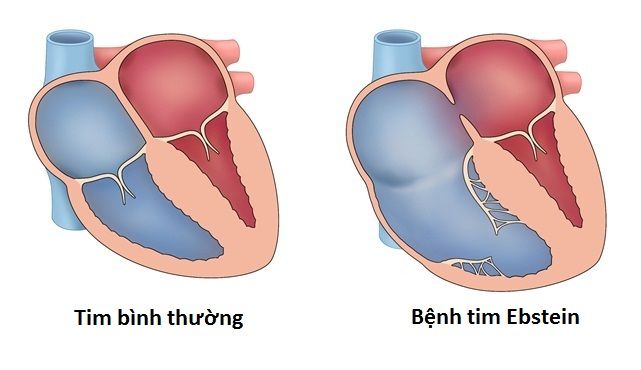

Ebstein là một dị tật tim bẩm sinh hiếm gặp, đặc trưng bởi lá van ba lá bám xuống thấp bất thường vào trong thất phải. Khi vị trí bám thay đổi, một phần thất phải bị nhĩ hóa, tức là hoạt động giống buồng nhĩ hơn là buồng thất.

Hậu quả là nhĩ phải giãn to, thất phải thực sự nhỏ lại và dòng máu qua van ba lá có thể bị hở. Nếu hở nhiều, máu trào ngược về nhĩ phải gây tăng gánh thể tích. Lâu dần có thể dẫn đến suy tim thai hoặc phù thai trong trường hợp nặng.

Trong tim bình thường, van ba lá nằm giữa nhĩ phải và thất phải, đảm bảo máu đi một chiều. Ở Ebstein, một hoặc nhiều lá van bám lệch xuống phía mỏm tim. Khoảng lệch này quyết định mức độ nặng.

Nếu lá van bám rất thấp, phần thất phải phía trên van sẽ không tham gia co bóp hiệu quả. Điều này làm giảm thể tích tống máu lên động mạch phổi. Đồng thời, hở van ba lá có thể xuất hiện do cấu trúc van bất thường.